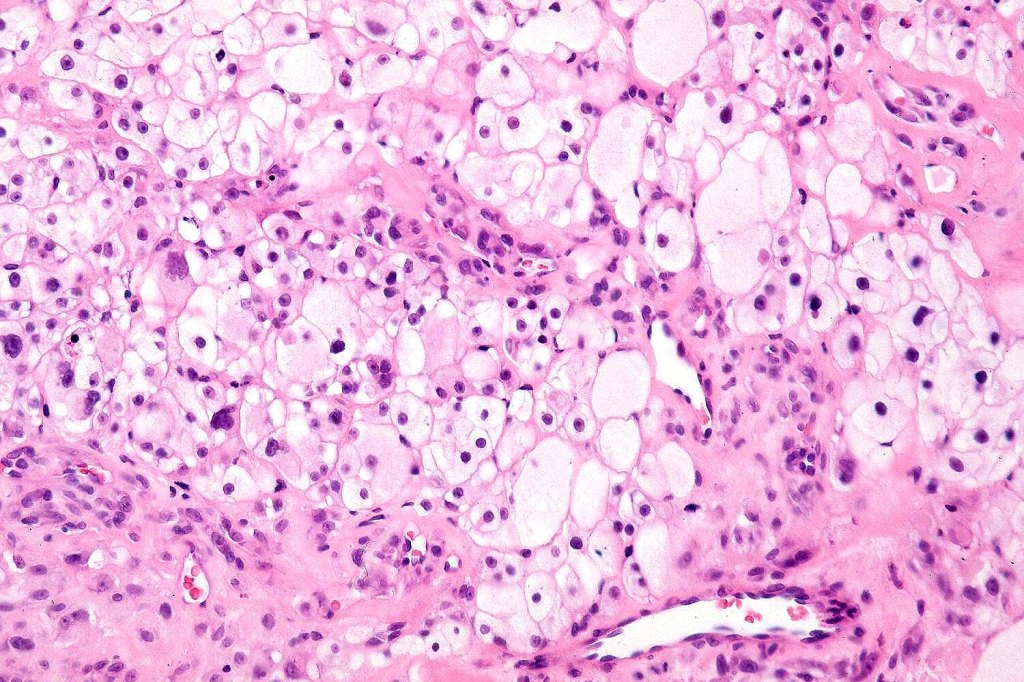

Histological features

•May affect the tumor in part or whole

•Enlarged cells with copious eosinophilic, foamy or clear cytoplasm (some authors include melanoma with clear cell change in the same category)

•Variable pigmentation

•Nuclei vesicular or hyperchromatic

•Pleomorphism is not generally marked and indeed can be very subtle

•Thought to be a result of abnormal or degenerative melanosome change